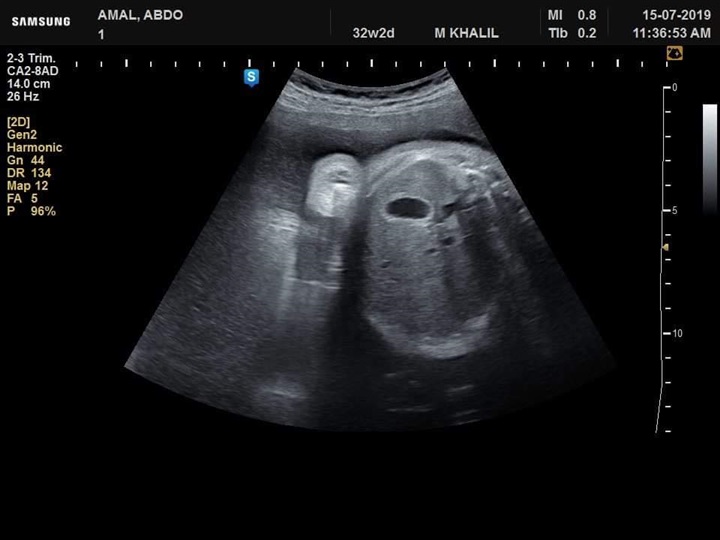

نجح فريق طبي من قسم النساء والتوليد في مستشفى جامعة كفر الشيخ في تشخيص  حالة تم تحويلها إلي مستشفي الجامعة بسبب وجود زيادة في السائل الامنيوسي، وبعد توقيع الكشف وتصوير للجنين تفصيليا تم اكتشاف وتشخيص جنين داخل رحم أمه وبه انسداد المرئ ووجود ناصور بين القصبة الهوائية والمرئ

عدم تكوين الجسم الثفني الذي يصل فصي المخ سويا وجود تشوه في القدم وابتعاد ألاصبع الكبير للقدم عن الإصبع الآخر وزيادة في السائل الامنيوسي تم بذل لتر و ٨٠٠ سم من السائل الأمنيوسي وإرسال بعضه للتحليل الكروموسومي.

وأوضح الفريق الطبي في قسم النساء والتوليد بمستشفى جامعة كفرالشيخ برئاسة الأستاذ الدكتور محمد خليل أنه تم تشخيص حالة أخري استسقاء لجنين داخل الرحم لأسباب جينية وحالة أخري بضمور كليتي الجنين وهذا التشخيص المبكر يساعد علي مساعدة الجنين الأول بعمل عملية له بعد الولادة لإصلاح الانسداد بالمرئ وإصلاح الناصور أما في الحالتين الثانيتين فينصح بعدم تعرض الأم لعمل عملية قيصرية في مثل هذه الحالات.